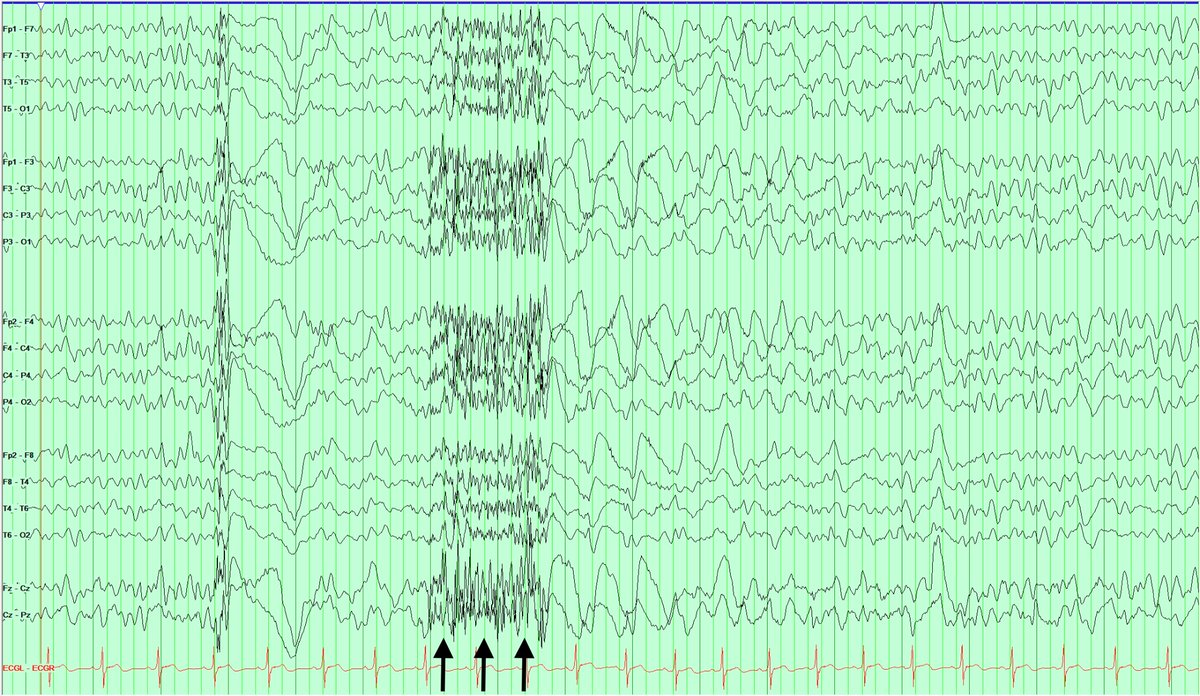

6/15/23

Emory EEG Case of the Day #311

Hx: 20M with Down syndrome, multiple seizure types including atonic seizures refractory to ASMs

Q:

1) What do you see denoted by the black arrows?

2) What is the likely diagnosis?

@EmoryNeurology Yes, it's GPFA and LGS! Congrats to @Vijay_kataria @Abd_Hed @DrAlshami @LokeshS34998102 @sushantshangari @tobeneurologist @drparekh13 @cychuan @serdaroglu_ayse @paedneurophile @agirlfromschool @Diaz88A @BalajiAs15 @drdips23 who got it! 👊🧠🏆